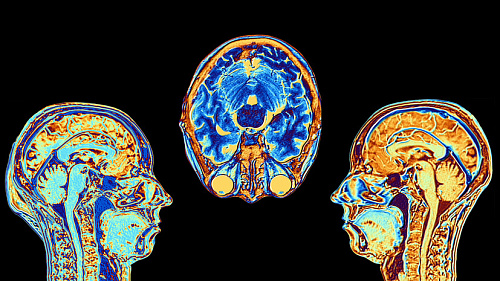

«Понять природу психических расстройств»: российские ученые создали подробную «карту жирности» мозга

Российские ученые создали «карту жирности» человеческого мозга, которая показывает распределение л...